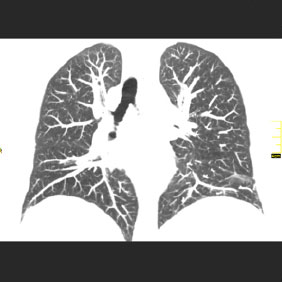

Tomografía computarizada Tórax

< Volver a "Tomografía Computarizada (TC) con Inteligencia artificial"Se utiliza para el estudio de los pulmones y diferentes estructuras del tórax (mediastino, ganglios, costillas,…)